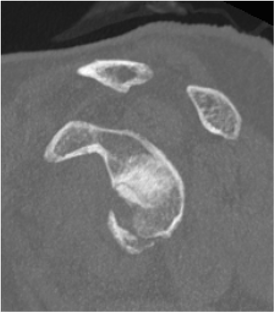

Type IV: Fracture of the glenoid fossa exiting medially

Definition

Similar to Ideberg Type III

- larger superior fragment